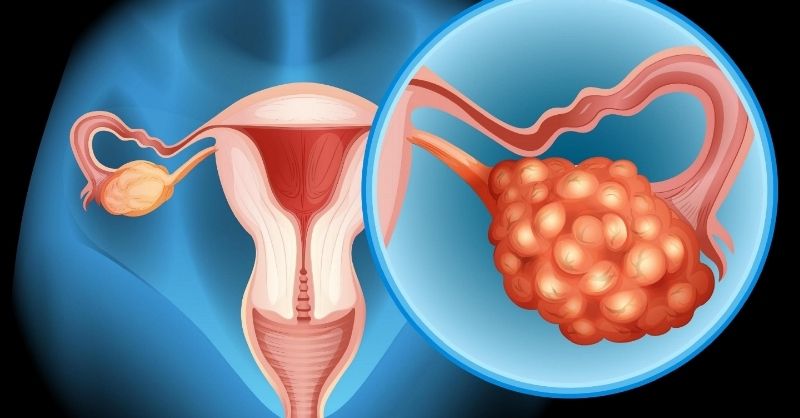

Recognizing Early Signs of Ovarian Cancer

Ovarian cancer is often called the “silent threat” because its early symptoms can be vague or mistaken for common health issues. It begins when abnormal cells in the...